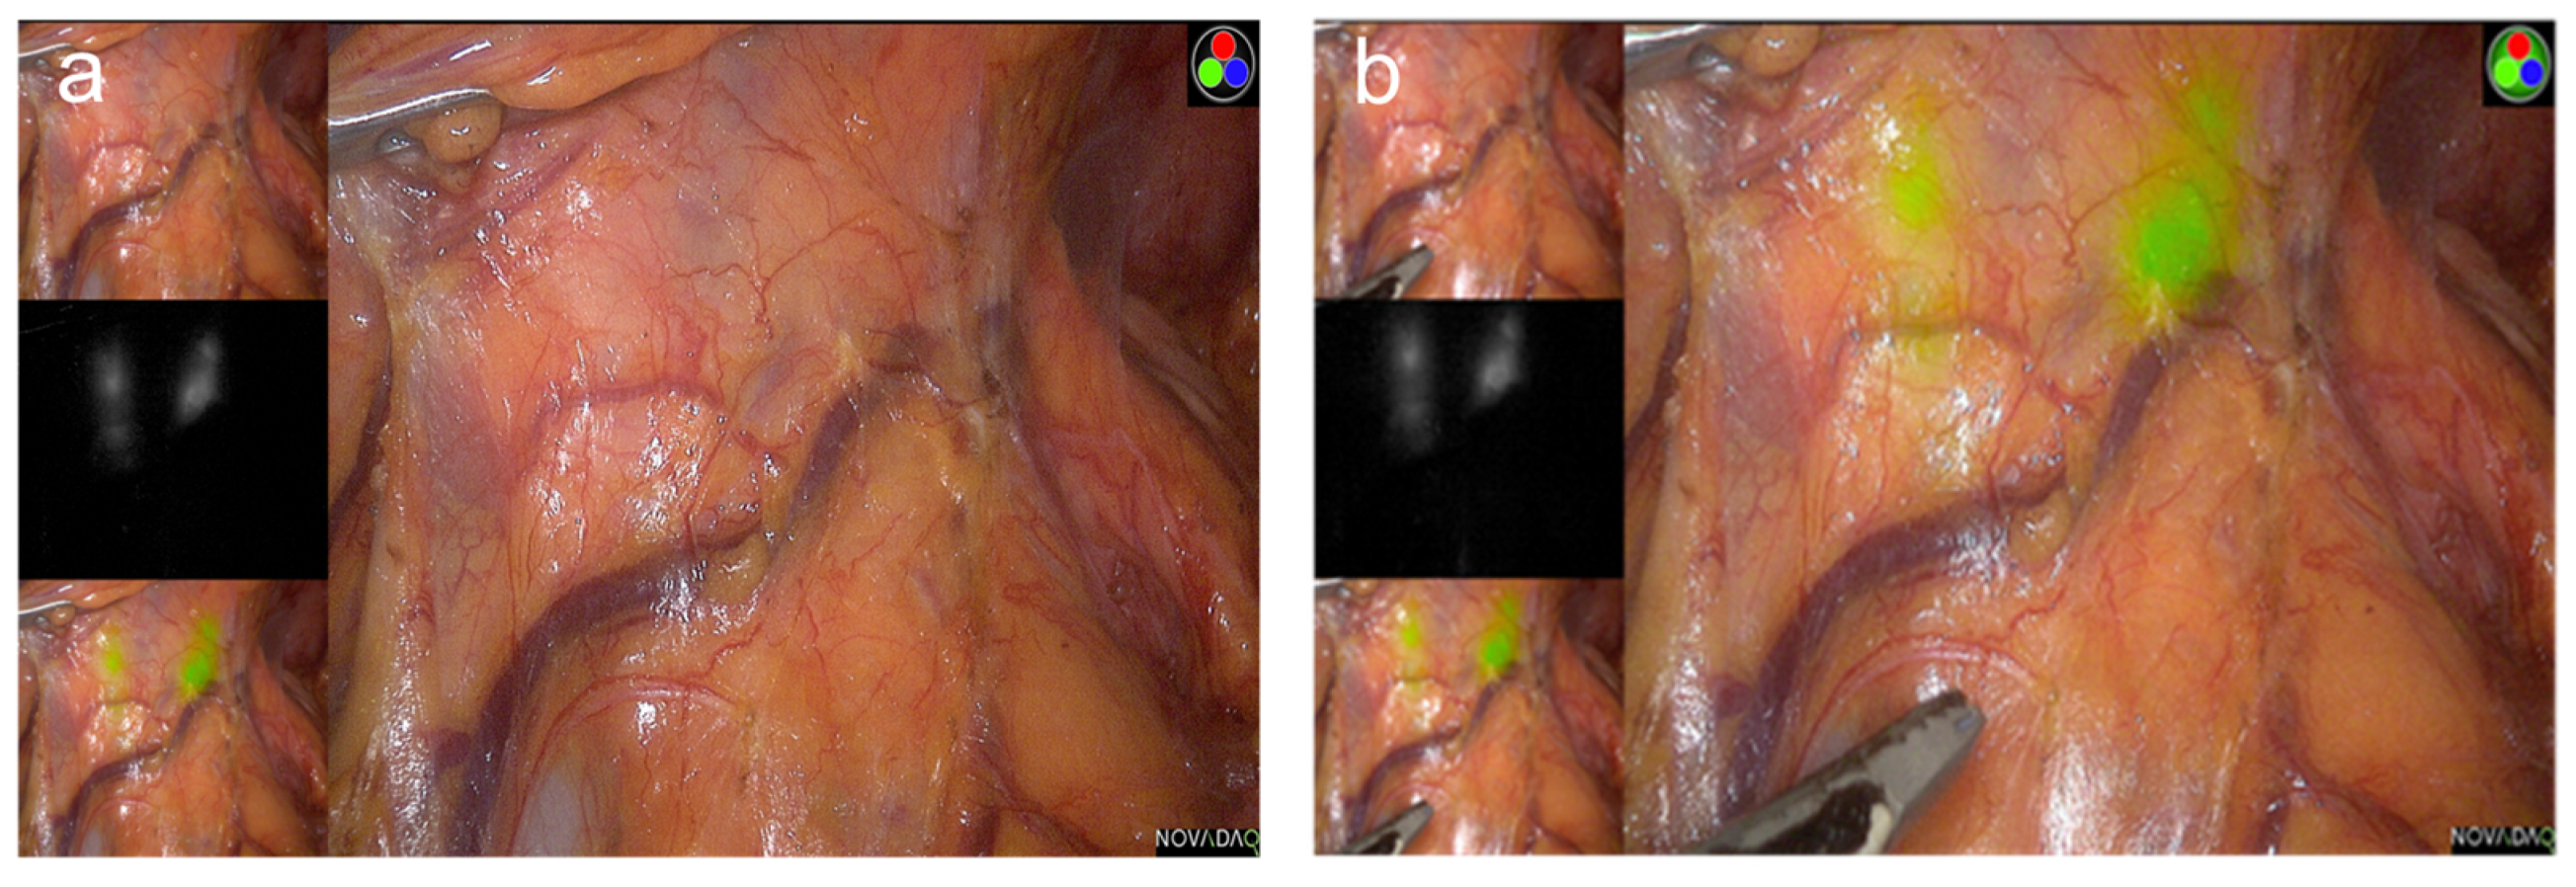

- Kim, M.; Son, S.Y.; Cui, L.H.; Shin, H.J.; Hur, H.; Han, S.U. Real-time vessel navigation using indocyanine green fluorescence during robotic or laparoscopic gastrectomy for gastric cancer. J. Gastric Cancer 2017, 17, 145–153. [Google Scholar] [CrossRef] [PubMed]

- Kim, T.H.; Kong, S.H.; Park, J.H.; Son, Y.G.; Huh, Y.J.; Suh, Y.S.; Lee, H.J.; Yang, H.K. Assessment of the completeness of lymph node dissection using near-infrared imaging with indocyanine green in laparoscopic gastrectomy for gastric cancer. J. Gastric Cancer 2018, 18, 161–171. [Google Scholar] [CrossRef] [PubMed]

- Kwon, I.G.; Son, T.; Kim, H.I.; Hyung, W.J. Fluorescent lymphography-guided lymphadenectomy during robotic radical gastrectomy for gastric cancer. JAMA Surg. 2019, 154, 150–158. [Google Scholar] [CrossRef] [PubMed]

- Park, S.H.; Berlth, F.; Choi, J.H.; Park, J.H.; Suh, Y.S.; Kong, S.H.; Park, D.J.; Lee, H.J.; Yang, H.K. Near-infrared fluorescence-guided surgery using indocyanine green facilitates secure infrapyloric lymph node dissection during laparoscopic distal gastrectomy. Surg. Today 2020, 50, 1187–1196. [Google Scholar] [CrossRef] [PubMed]

- Huh, Y.J.; Lee, H.J.; Kim, T.H.; Choi, Y.S.; Park, J.H.; Son, Y.G.; Suh, Y.S.; Kong, S.H.; Yang, H.K. Efficacy of assessing intraoperative bowel perfusion with near-infrared camera in laparoscopic gastric cancer surgery. J. Laparoendosc. Adv. Surg. Tech. A 2019, 29, 476–483. [Google Scholar] [CrossRef]